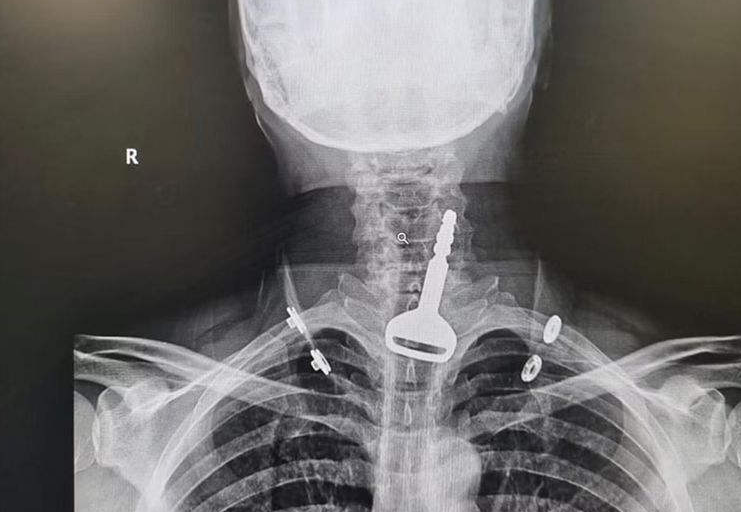

Bei Röntgenuntersuchungen wurde ein Autoschlüssel in den Atemwegen gefunden.

Wie Gulf News berichtet, wurde der 49-jährige Mann in die Notaufnahme des Krankenhauses eingeliefert, wo das Personal feststellte, dass er Atemprobleme hatte. Bei Röntgenuntersuchungen wurde ein Autoschlüssel in den Atemwegen gefunden, und der Patient erklärte den Ärzten, er habe ihn versehentlich verschluckt, als er mit ihm spielte. Es wurde beschlossen, dass eine Endoskopie zur Entfernung des Schlüssels und zur Beseitigung der Blockade der Atemwege die beste Lösung sei, aber die Tatsache, dass der Mann ein Herzpatient war, machte den Eingriff sehr viel komplizierter.